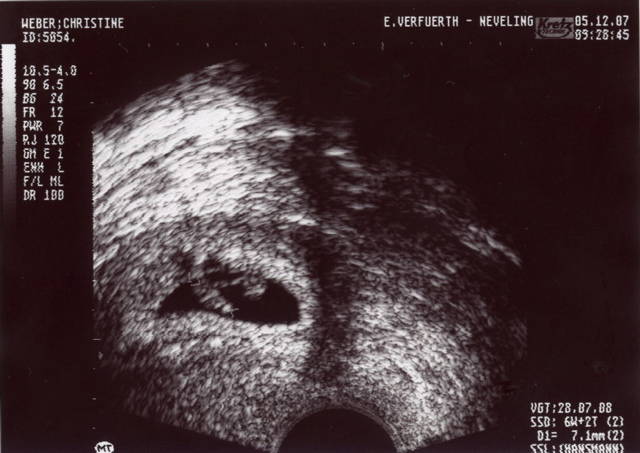

Mama und Papa haben mir freundlicherweise Bilder von meiner Ein-Zimmer-Wohnung zur Verfügung gestellt. Erstellt wurden die mit so einem Ding namens Ultraschall. Ich weiß nur noch, dass ich in den ersten Wochen von dem Teil überhaupt nicht begeistert war und mich immer ganz klein gemacht habe, wenn Mama und Papa schon wieder knippsen wollten. Aber wer lässt sich schon gern freiwillig in seine Privatsphäre schauen?

Hier seht ihr mich als "Würmchen" – eine ganz kleine Bohne.

Hier ist bin ich schon etwas größer – 7mm.